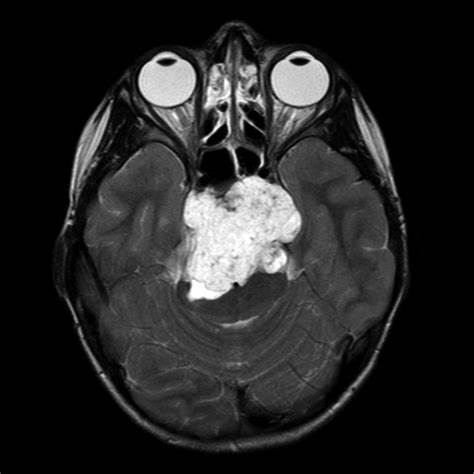

雯雯脊索瘤影像图